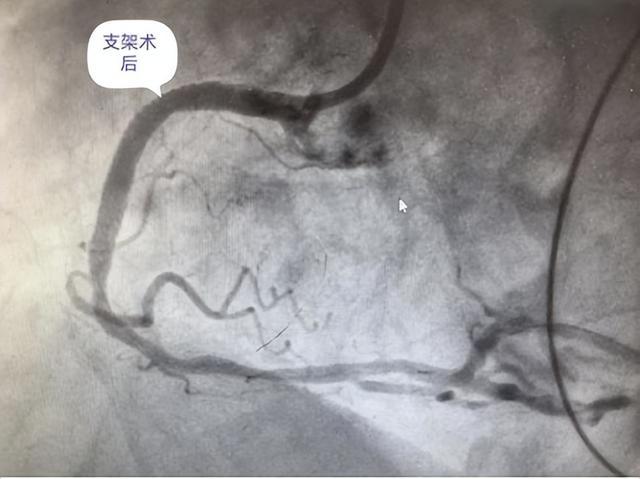

术后造影显示血管恢复通畅,支架贴壁完美,贺大爷胸痛症状完全消失。

【术后复查】